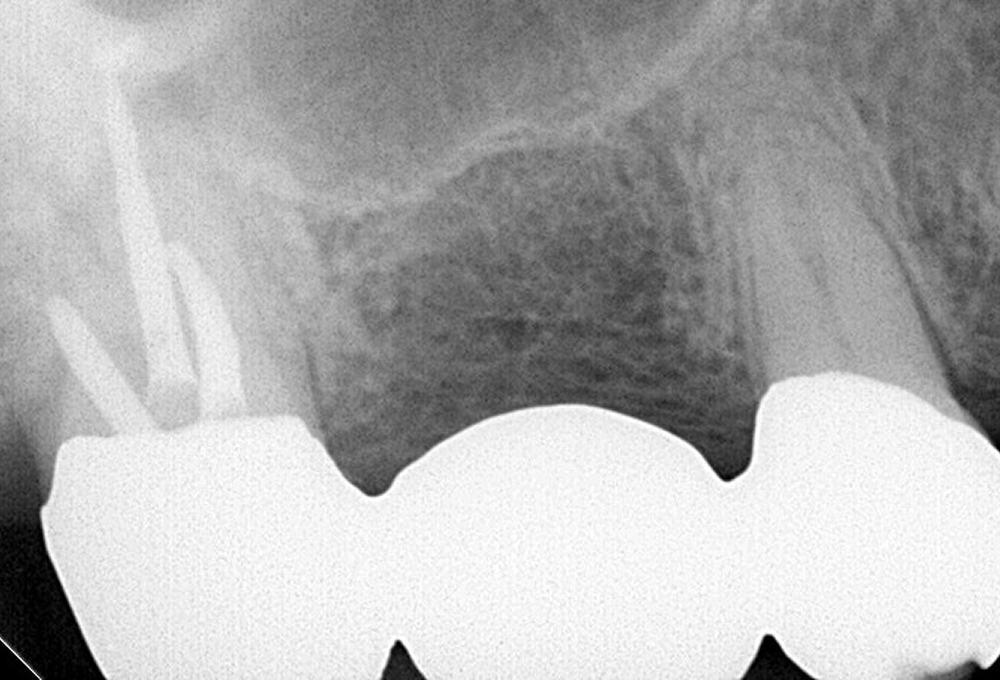

①術前 歯冠大の根尖病変